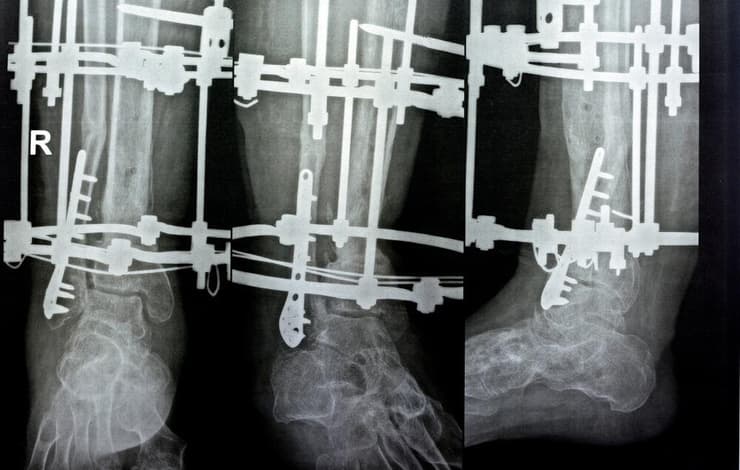

פרופ' אידלמן מסביר כי ניתוח הארכת גפיים מתבצע בכמה שלבים. "תחילה שוברים באופן מבוקר את העצם שברצוננו להאריך, למשל עצם הירך או השוק". בהמשך, מרחיקים בין חלקי העצם. בשלב זה, ניתן לקבע את המצב באמצעות מתקן חיצוני - מתקן מתכתי שמורכב סביב הרגל, עם טבעות ומסמרים שחודרים דרך העור ומתחברים לעצם. "המתקן מאפשר שליטה מדויקת על תהליך ההארכה, כאשר המטופל או הצוות הרפואי מסובבים מוטות בקצב של מילימטר בכל יום", מסביר פרופ' אידלמן.

3 צפייה בגלריה

בשיטה המסורתית, הקיבוע מתבצע באמצעות פינים שחודרים את שכבת השריר - הליך שכרוך בכאב רב. ארכיון